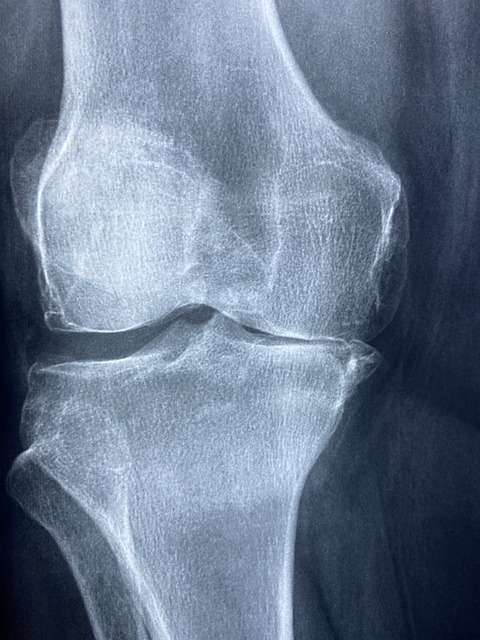

무릎은 우리 몸에서 다리의 움직임을 지탱하고 통제하는 중요한 역할을 합니다. 일상 생활에서 무릎의 부담이 적지 않기 때문에, 우리는 무릎 건강을 신경써야 합니다. 무릎은 다른 관절에 비해 부상에 취약할 수 있으며, 이러한 문제를 예방하기 위해서는 꾸준한 운동과 관리가 필요합니다. 같은 동작을 반복하거나 부적절한 운동은 무릎에 과도한 부담을 줄 수 있으므로, 이를 보완할 수 있는 요가 동작이 필요합니다.

무릎은 인체에서 가장 중요한 관절 중 하나로, 하체의 움직임을 지탱하는 역할을 합니다. 요가를 시작하기 전, 자신의 무릎 상태를 점검하는 것이 필수입니다. 팔꿈치나 손목과는 달리 무릎은 쉽게 부상을 입을 수 있어요. 운동을 시작하기 전에 다음과 같은 사항을 확인해보세요: